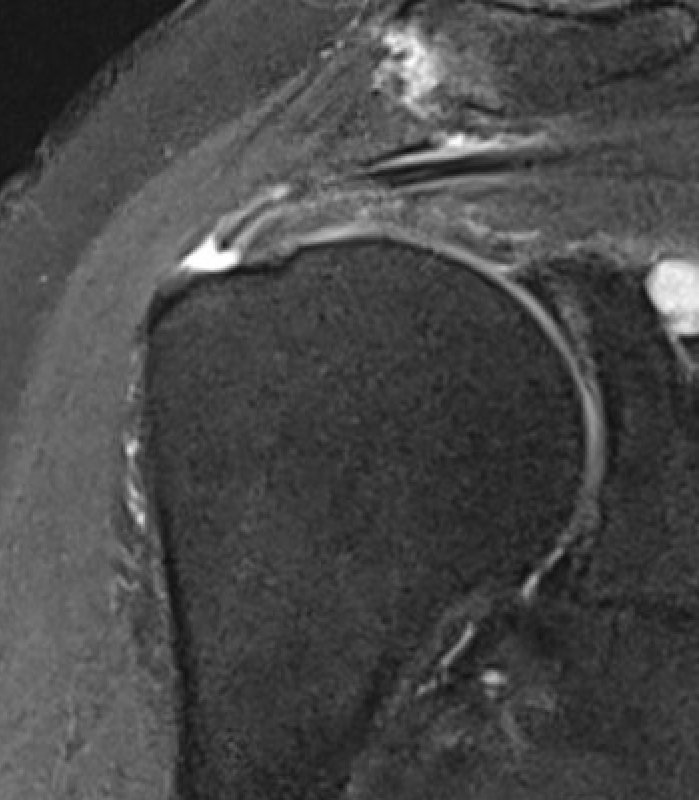

Full thickness rotator cuff tears

Partial bursal sided tear Partial articular sided tears

Small full thickness rotator cuff tear of supraspinatus - retracted to footprint

Large full thickness tear of supraspinatus and infraspinatus tendon - retracted to midhumeral head

Massive rotator cuff tear of the supraspinatus and infraspinatus tendon - retracted to glenoid